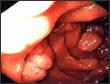

Coloscopie (Bx systématiques)

- RCH: ATCD familiaux, manifs extra intestinales Atteinte rectale constante, lésions continues

- Maladie de Crohn ATCD familiaux, manifs extra intestinales lésions anales, atteintes segmentaires Histo: granulome tuberculoïde, fissurations

- Amibiase Sd dysentérique, ulcérations « coup d’ongle » Parasitologie selles et Bx

- Muqueuse « normale »: BIOPSIES +++

. Colites microscopiques (collagène, lymphocytaire)